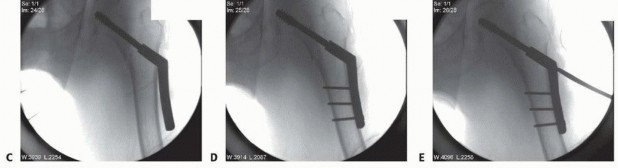

** Fracture Reduction With the patient conscientiously positioned on the fracture table, the fracture is initially reduced in the coronal plane with axial traction to reestablish fracture length and partially correct the varus malalignment ( TECH FIG 1). Abduction of the leg usually corrects varus malalignment and establishes the normal neck-shaft angle. Internal rotation of the distal extremity usually corrects the external rotation at the fracture. Internal rotation also serves to align the femoral neck parallel to the floor and assist in eventual guide pin insertion. In some instances, external rotation of the proximal fragment is necessary to achieve reduction of the rotational deformity.

### TECH FIG 1 • Fracture reduction. A. Preoperative peritrochanteric fracture. B. Position of the fracture after longitudinal traction. C. Position of the fracture after longitudinal traction and abduction applied. D. Position of the fracture after longitudinal traction, abduction, and internal rotation applied. E. Posterior fracture sag. F. Position of the fracture after longitudinal traction, abduction, internal rotation, and flexion force applied with a crutch under the leg. G. Intraoperative picture of crutch placed under distal fragment. Fracture reduction is next checked in the lateral plane. The distal femur tends to sag posteriorly while the proximal fragment is flexed by the iliopsoas. This can be corrected by placing a crutch under the femoral shaft for support. Alternatively, some fracture tables have padded attachments to support the thigh. Fracture reduction is reassessed in both the AP and lateral planes and checked for neck-shaft angle, neck anteversion, rotation, and femoral shaft sag, with a goal of obtaining a near-anatomic reduction. Acceptable parameters include normal or slight valgus reduction, less than 20 degrees of angulation on the lateral radiograph, and less than 4 mm of fracture translation. 1 If a near-anatomic closed reduction cannot be obtained, percutaneous techniques can include use of Schanz pins, a bone hook, or an elevator used to manipulate fracture fragments. In the event that reduction is still inadequate, open reduction is necessary. 407 1. ## Side Plate and Sliding Hip Screw ### Approach Because of the muscular forces exerted on the fracture fragments associated with peritrochanteric hip fractures, anatomic reduction of the fracture is close to impossible with indirect methods, especially in the coronal plane, which is often the most difficult plane to control.** Studies have shown that absolute anatomic reduction of all fragments of these fractures is not necessary for a satisfactory functional outcome. 14 The primary goal of reduction of peritrochanteric hip fractures is to reestablish a normal anatomic alignment between the proximal head and neck fragment and the distal femoral shaft in the coronal, sagittal, and axial planes. A lateral approach to the proximal femur is the preferred approach for open reduction and internal fixation of peritrochanteric femur fractures. This approach may be used whether the selected implant is a side plate, a blade plate, or a proximal femoral locking plate. The incision is centered over the lateral aspect of the femur. Its proximal extent is the palpable vastus ridge for sliding hip screw devices and just proximal to the tip of the greater trochanter for fixed-angle plates. The distal extent of the incision is made long enough to allow application of the plate.